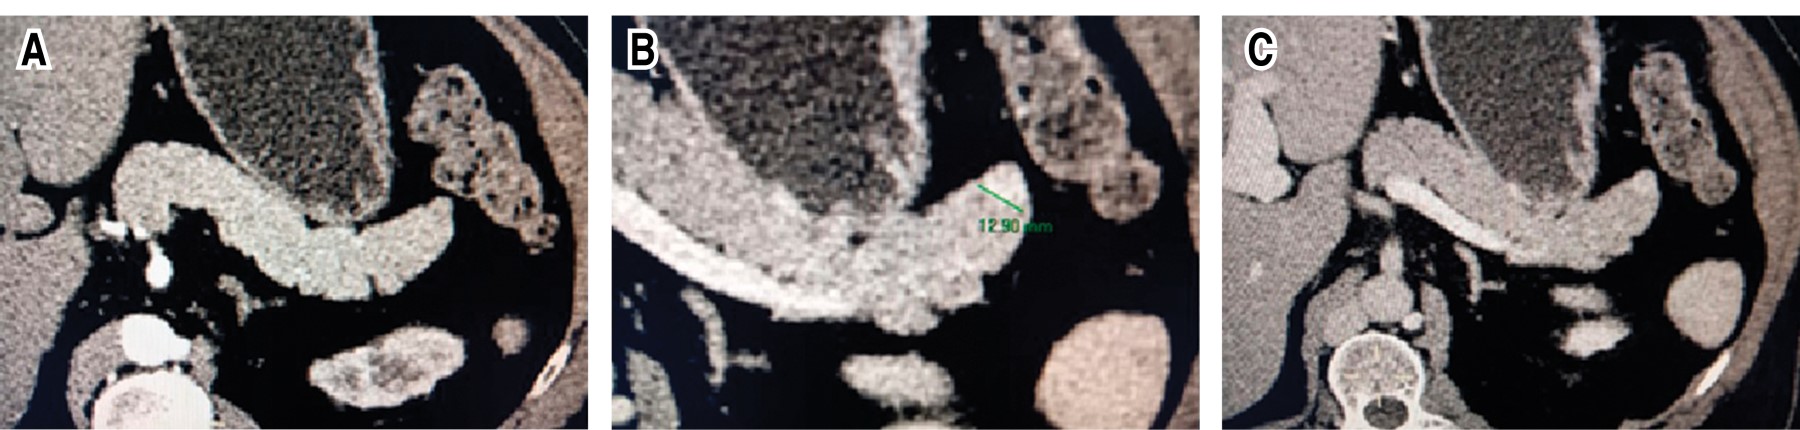

En múltiples ocasiones requirió atención en el servicio de urgencias dónde se evidenció la presencia de hipoglucemia tratada con solución glucosada que mejoraba el cuadro clínico. En general la exploración física dentro de parámetros normales, peso de 90 kg, talla 170 cm, índice de masa corporal (IMC) 31.1. Como parte del abordaje diagnóstico se realizó una prueba de ayuno que se tuvo que suspender después de 18 horas por síntomas neuroglucopénicos. Se identificó hiperinsulinismo sérico con glucosa de 56 mg/dL, insulina de 79 Uu/mL, péptido C de 10.2 ng/mL y relación insulina/glucosa de 13.1. Se solicitó una tomografía computada helicoidal trifásica, la cual demostró un nódulo redondo, de contornos bien delimitados, sólido, de localización superficial en la porción distal de la cola del páncreas que mide 12.9 mm de diámetro, hipodensa en la fase arterial e hiperdensa en las fases porta y principalmente en la fase venosa, la opinión radiológica fue de sospecha para insulinoma (Figura 1). Por las conclusiones de los estudios de imagen, la paciente se programó para pancreatectomía distal por laparoscopia que se realizó sin complicaciones. El estudio histopatológico reportó un fragmento de páncreas de 3.5 × 3 × 2.5 cm, amarillo rosado, se identificó lesión esférica, única de superficie gris violácea de 1.5 × 0.9 × 0.9 cm. Se identificó hiperplasia de los islotes pancreáticos y células endócrinas aisladas, así como bazo accesorio en la cola del páncreas. La inmunohistoquímica reveló positividad a sinaptofisina y cromogranina en los islotes pancreáticos de Langerhans con un índice de proliferación ki67 de 1%. Con todos estos datos se realizó el diagnóstico de nesidioblastosis difusa (Figuras 2 y 3). En este momento el paciente se encuentra con adecuado control glucémico y remisión de los eventos neuroglucopénicos.

Figura 1